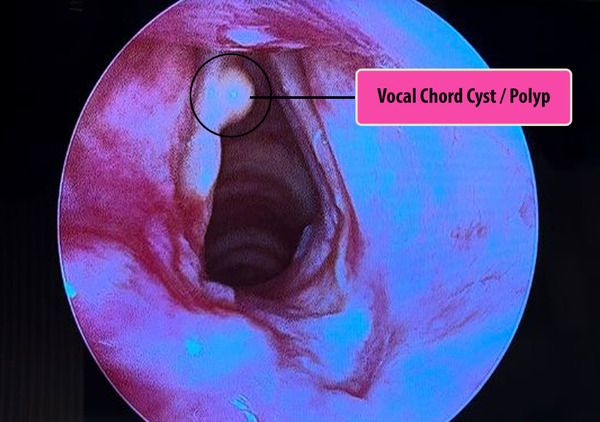

Understanding Vocal Cord Cysts and Their Impact

Vocal cord cysts are benign lesions that can significantly affect the quality of voice and speech. These cysts, which may be caused by straining vocal chords or congenital factors, often present symptoms such as hoarseness, voice fatigue, and loss of vocal range. Left untreated, these cysts can lead to chronic vocal problems, severely impacting a person’s quality of life.

The Microflap Technique: A Closer Look

The microflap technique is performed under general anesthesia, ensuring patient comfort and safety. This is a natural orifice surgery done with a state-of-the-art 4k hd camera and monitor. Laser is used for excision and hemostasis in a few cases. Using a high-powered microscope, a small flap is created on the vocal cord. This allows for direct access to the cyst, which is then carefully removed. The microflap is repositioned, allowing the vocal cord to heal naturally.